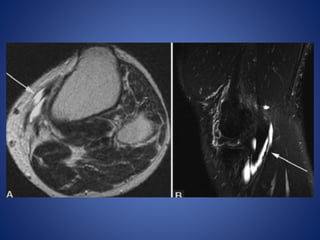

• #7 Popliteal cyst. (A) radiograph demonstrates coarse calcifications (arrow) in the popliteal fossa. (B) USG image at the level of popliteal fossa demonstrates a cystic lesion containing echogenic calcifications (arrow) with posterior acoustic shadowing. (C) Axial T2W image through right knee demonstrates the hyperintense popliteal cyst fluid arising between semimembranosus (arrowhead) tendon and medial head of gastrocnemius (asterisk), with hypointense loose bodies (arrow) layering dependently